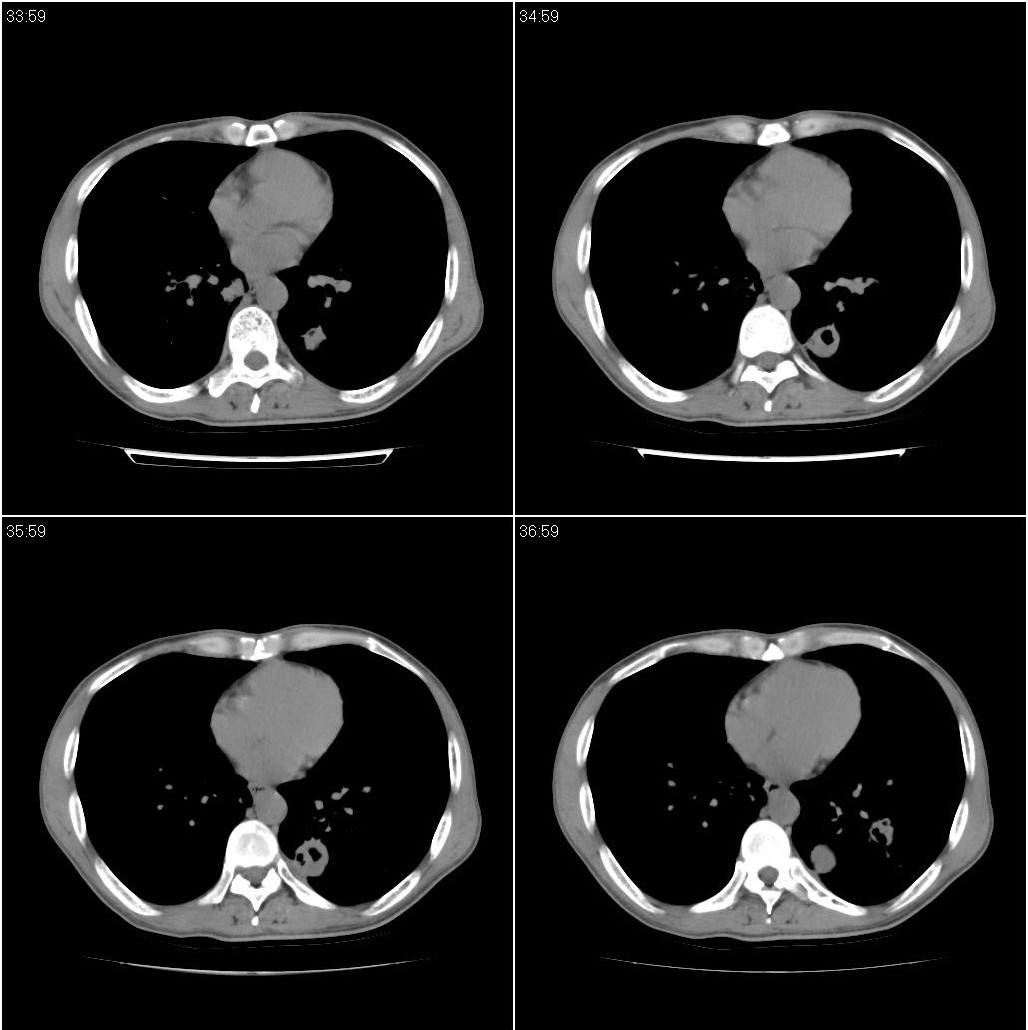

标题: CT23980:男性,47岁。近来咳痰、咳血,血沉增快(40左右),

男性,47岁。近来咳痰、咳血,血沉增快(40左右),痰中未检出结核杆菌。

两肺继发性肺结核并多发性结核球形成,部分病灶内空洞形成。

符合继发性结核表现部分空洞形成并播散